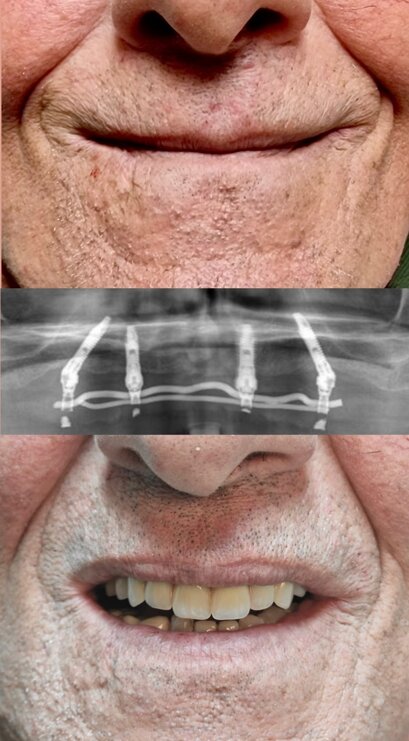

IMPLANTOLOGIA

Protesi fissa su impianti endossei

Riabilitazione orale completa con tecnica All-on-4: Inserimento di quattro impianti dentali su cui viene fissata una protesi fissa, per ripristinare funzionalità ed estetica del sorriso in modo stabile e immediato.